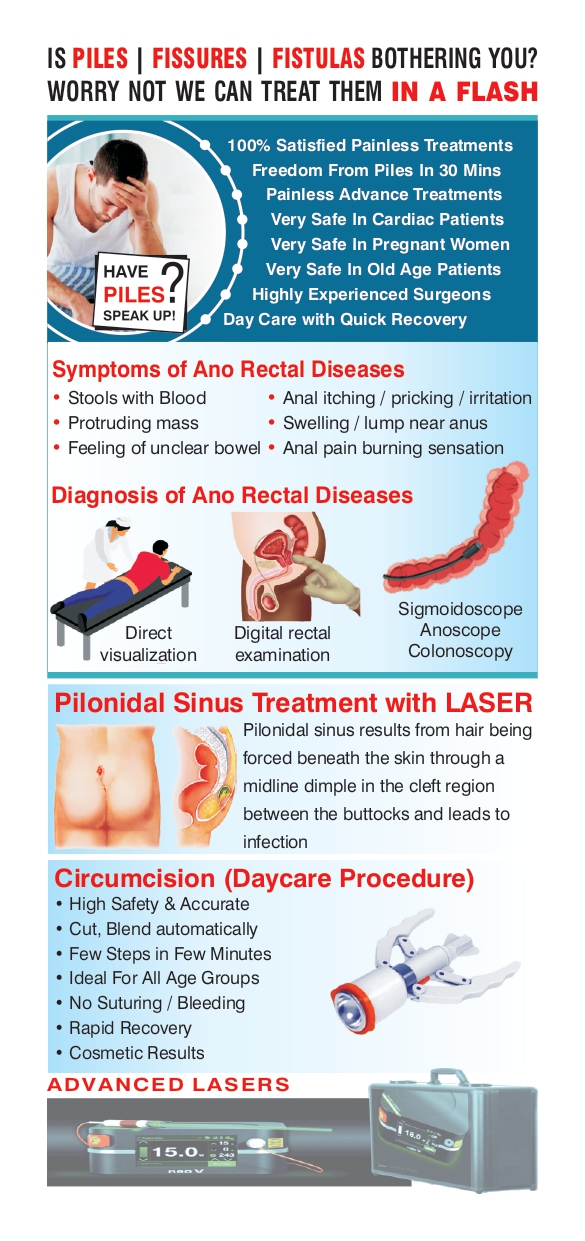

TREATMENTS WE OFFER ( SERVICES )

Piles

Hemorrhoids (HEM-uh-roids), also called piles, are swollen veins in the anus and lower rectum. Hemorrhoids are similar to varicose veins. Hemorrhoids can develop inside the rectum, called internal hemorrhoids. They also can develop under the skin ar

Fissures

Fissures result from the stretching of your anal mucosa beyond its normal capacity. This often happens when stools are hard due to constipation. Once the tear happens, it leads to repeated injury. The exposed internal sphincter muscle beneath the tear goes

Fistulas

Pilonidal Sinus

An abnormal skin growth located at the tailbone that contains hair and skin.The cyst is usually located near the tailbone and can become easily infected.

Symptoms of an infected cyst include pain, reddened skin or drainage of pus or blood.

Treatment involves drainage and surgical removal of the cyst.